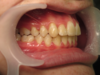

Cas n°10 traité par multi-attaches - adolescent

Ce cas d’adolescent démontre l'efficacité du traitement par brackets autoligaturants pour résoudre un encombrement majeur sans extraction. Initialement, le patient présentait des dents sévèrement chevauchées et exclues de l'arcade par manque de place.

Grâce à la technologie autoligaturante, le traitement a privilégié le développement biologique des arcades. Les forces légères et constantes ont permis d'élargir les arcades de manière physiologique, créant l'espace nécessaire pour aligner chaque dent tout en respectant l'équilibre du profil.

Résultats clés :

• Intégrité dentaire : Conservation de toutes les dents naturelles.

• Harmonie esthétique : Sourire large et aligné qui transforme l'expression faciale.

• Santé parodontale : Alignement facilitant l'hygiène et protégeant les tissus de soutien.

Ce traitement illustre parfaitement l'orthodontie moderne : une approche conservatrice qui optimise la fonction et l'esthétique sans compromis chirurgical ou extractif.